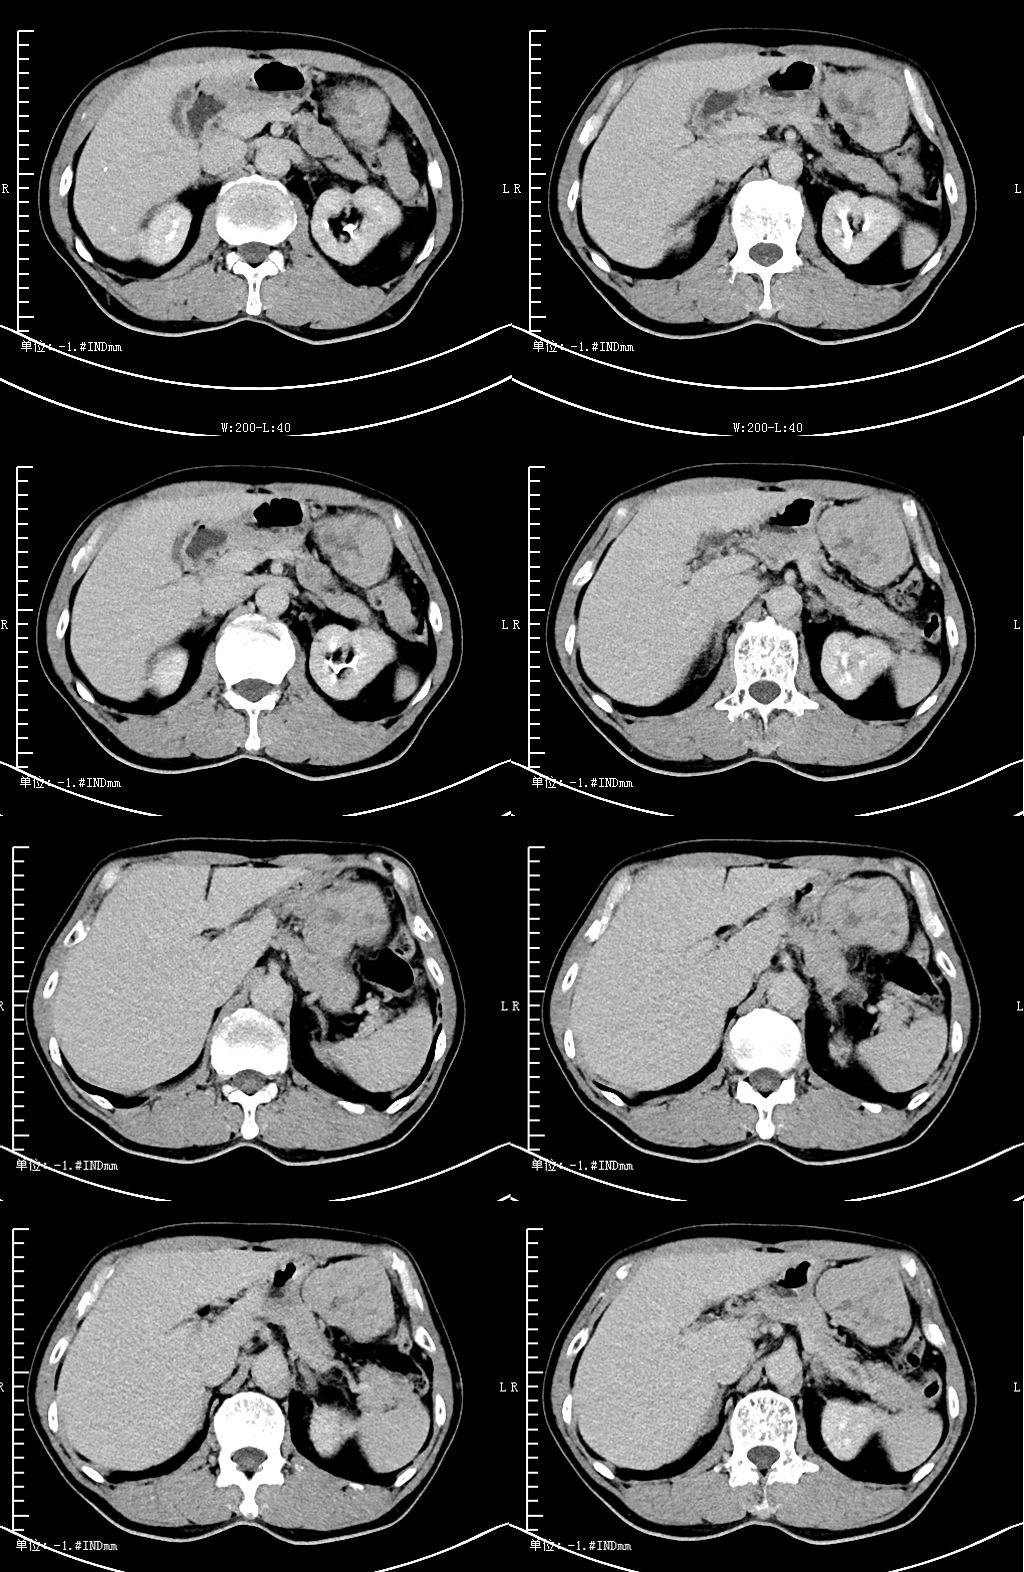

CT 平扫

CT 动脉期

CT 静脉期

CT 延迟期 医学百科网 | YxBaike.Com

CT 表现:胃大弯外侧见类圆形软组织密度影,边界清,相邻胃大弯受压,大小约 56×71×41 mm,其内见斑片状低密度影,边界欠清,增强扫描 CT 值约 47 HUPS、52-72 HuCE、延迟期 69 Hu,其内见斑片状影无强化。 医学百科网 | YxBaike.Com